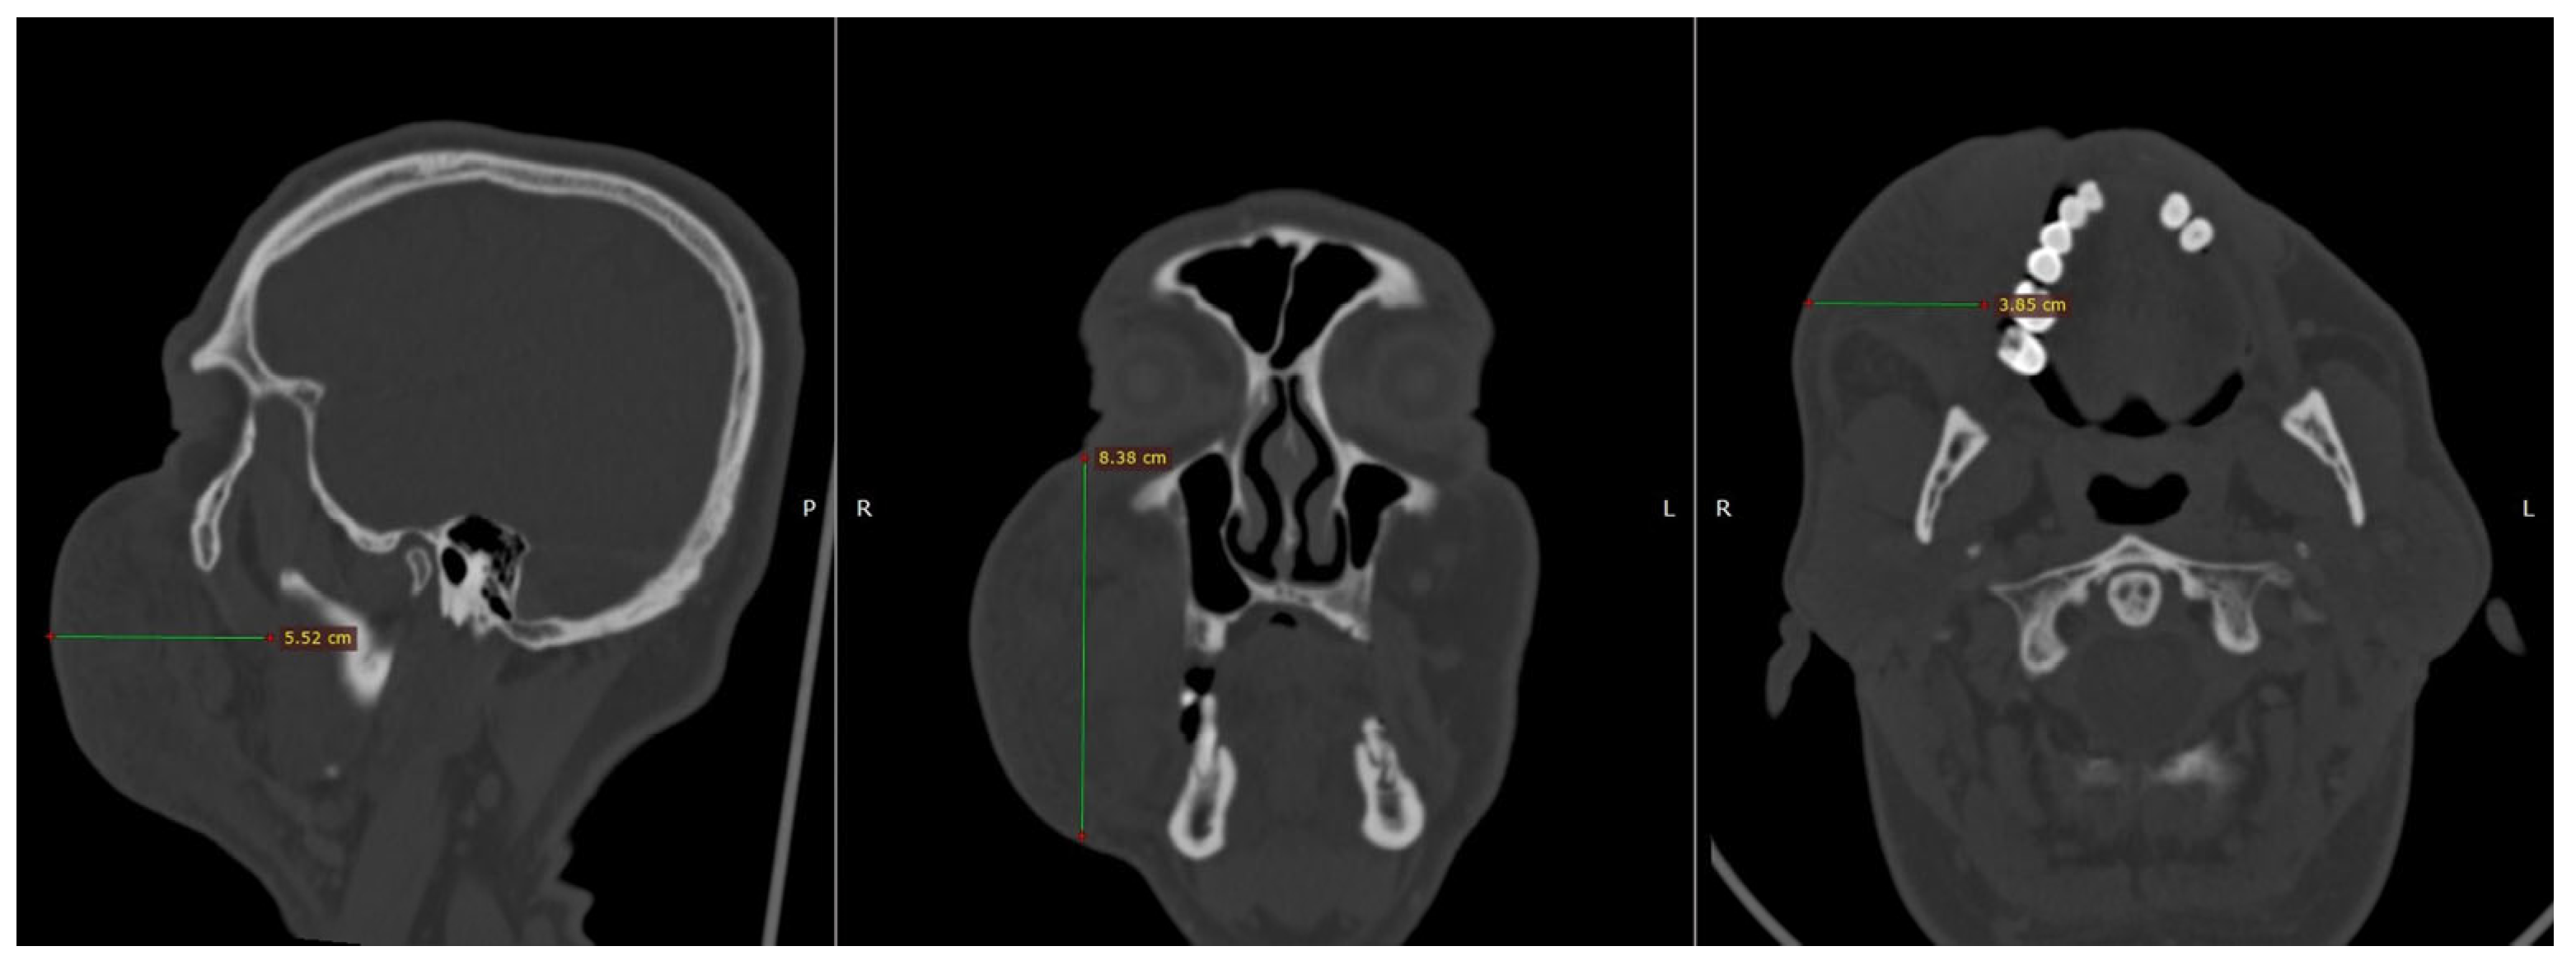

2. Case Presentation